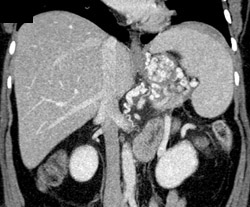

Gastric Hernia Through the Diaphragm